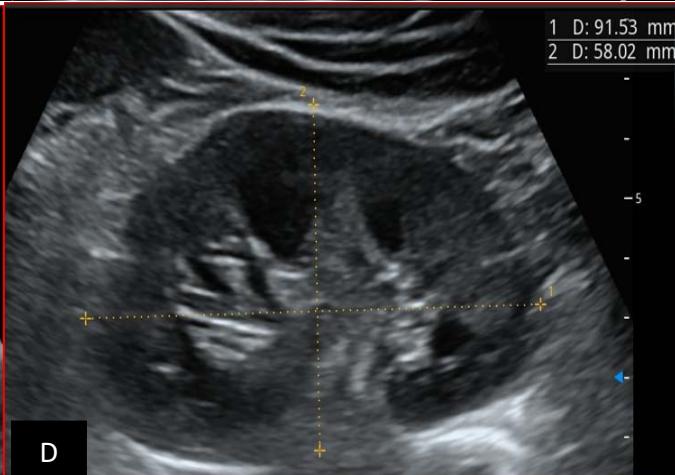

Figure 5: Abdominopelvic ultrasound control after 6 courses of chemotherapy in the same 3 year old patient with a ruptured left renal nephroblastoma; Images A, F, G, and H: show regression of the solid, endo and exo renal, left nephroblastoma mass treated with 6 courses of chemotherapy (current volume 430 ml vs) Images: B, C, and: show persistence of thrombotic permeation pan vena cava and ipsilateral renal. Image E: shows a volumetric regression of the intra-lesional hematic collection, at the tumor rupture estimated at 34.49 ml VS, Image I: represents the right kidney in B mode which is of normal echoculture. Source: Dr. Frederick Tshibasu Tshienda database.